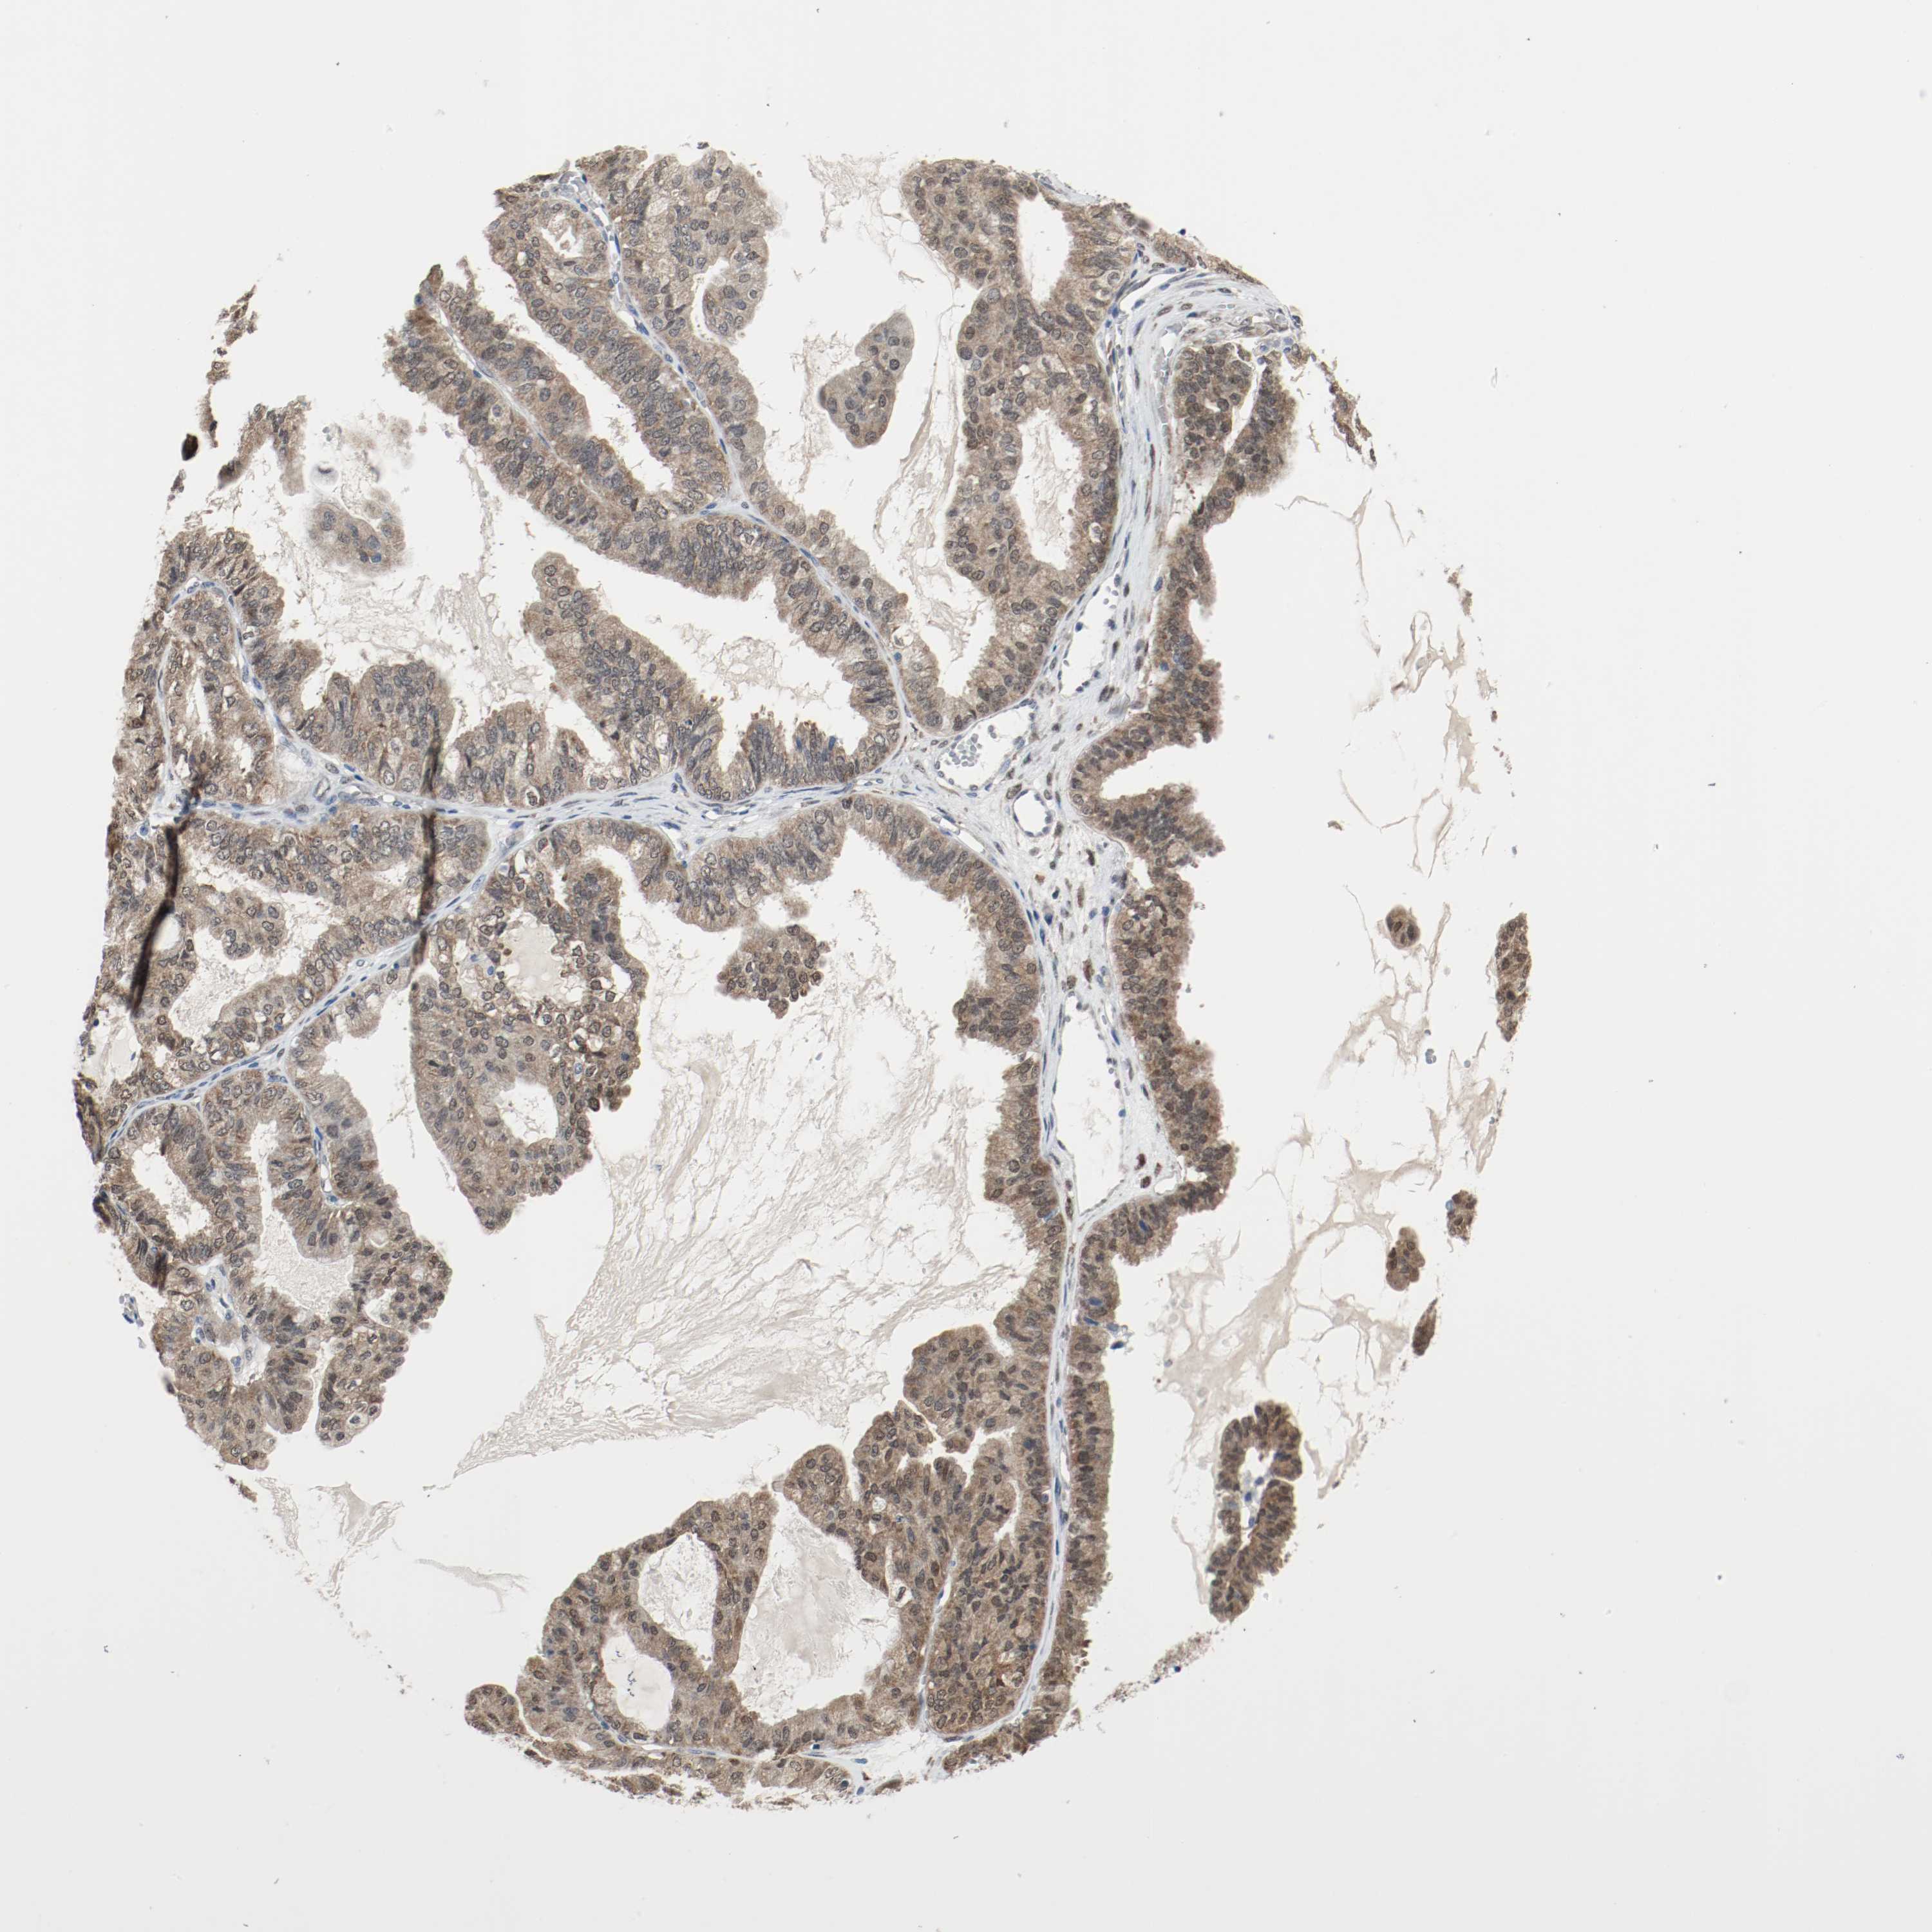

OVARIAN CANCER - Protein expressioni

A mouse-over function shows sample information and annotation data. Click on an image to view it in a full screen mode. Samples can be filtered based on level of antibody staining by selecting one or several of the following categories: high, medium, low and not detected. The assay and annotation is described here.

Note that samples used for immunohistochemistry by the Human Protein Atlas do not correspond to samples in the TCGA dataset.

Antibody stainingi

Antibody staining in the annotated cell types in the current human tissue is reported as not detected, low, medium, or high, based on conventional immunohistochemistry profiling in selected tissues. This score is based on the combination of the staining intensity and fraction of stained cells.

Each image is clickable and will lead to virtual microscopy that enables deeper exploration of all samples and also displays staining intensity scores, fraction scores and subcellular localization as well as patient and tissue information for each sample.

Antibody HPA043900

Antibody CAB004541

Staining

High

Cystadenocarcinoma, serous, NOS

Carcinoma, NOS

Cystadenocarcinoma, mucinous, NOS

Carcinoma, endometroid